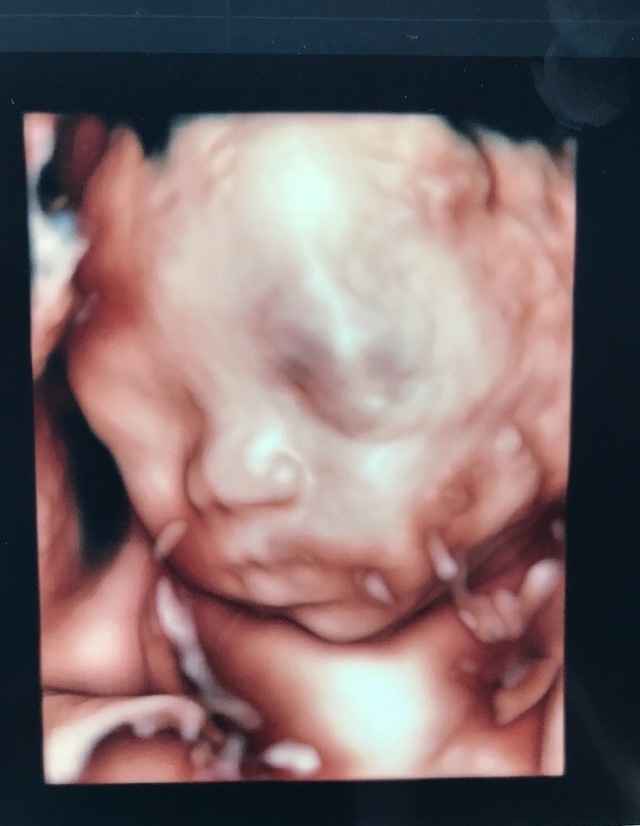

25週4日(25w4d・男の子)|はまくみ さん(31歳)

エコー写真撮影時のエピソード:

初めて4Dを撮った時のお気に入りショットです。

私が通っている病院は4Dがないので、他院の妊婦さんを4Dで受け付けている別の病院に、21週、25週、28週で通いました。こんなにリアルなお顔が見れてパパと感動して、ますます愛おしさが増しました。

一度流産を経験しての妊娠ですので、無事に産まれてくるまで不安も絶えませんが、こういう表情が見れると、楽しみが増しますよね!